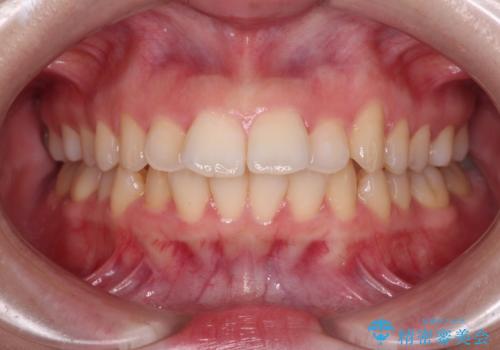

- 上下の前歯が突出しており、口が閉じにくいとのことで来院された患者様です。

上下前歯が著しく前突している状態であったので、上下左右の第1小臼歯4本を抜歯し、ワイヤー装置にて矯正治療を行うこととしました。

舌の突出癖があり、前歯の移動量も多くなるため、治療期間は長くなると予想されましたが、13ヶ月という予定の半分程度の期間で終えることができました。